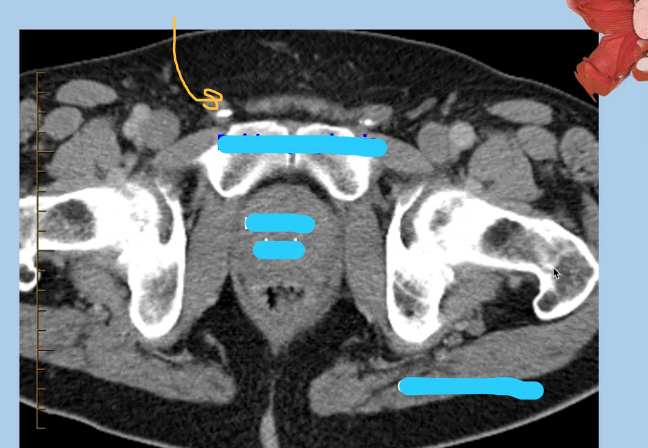

Identify > imaging modality > Pubic symphysis > Obturator foramen

CT: axial slice 1. Pubic Symphysis= A 2. Obturator foramen= C | In a MRI, fat would be wihte